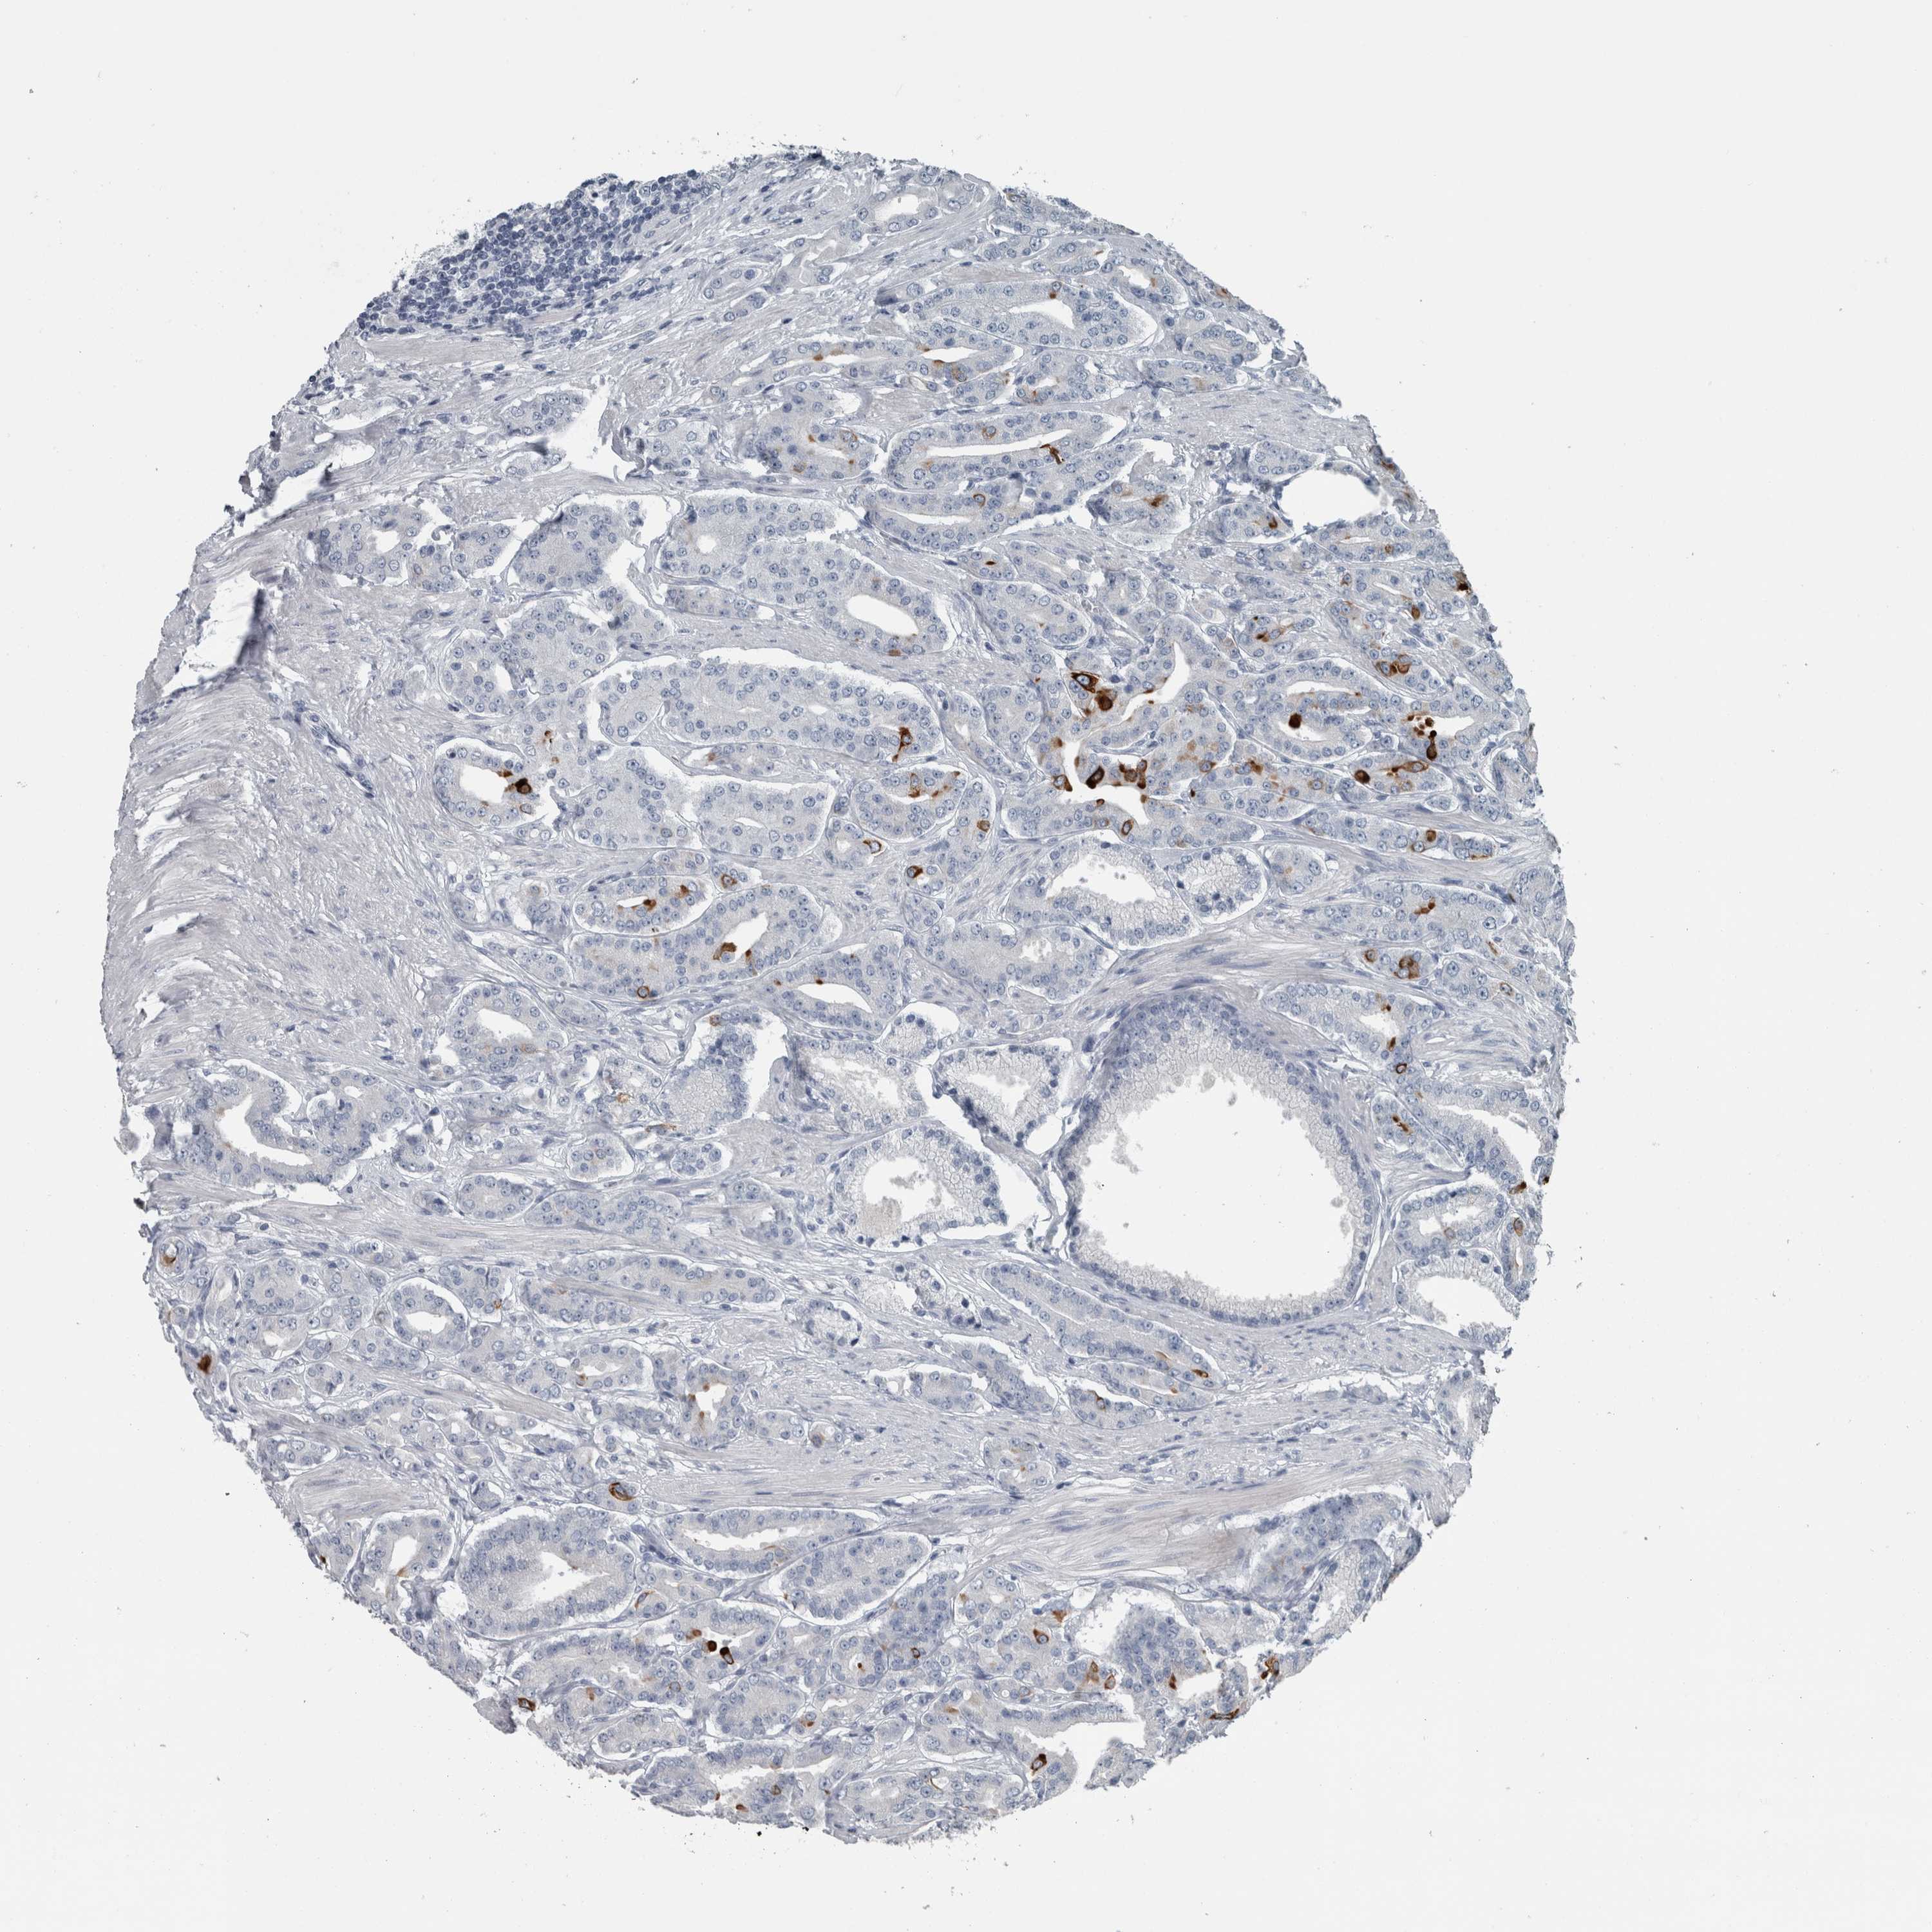

PROSTATE CANCER - Protein expressioni

A mouse-over function shows sample information and annotation data. Click on an image to view it in a full screen mode. Samples can be filtered based on level of antibody staining by selecting one or several of the following categories: high, medium, low and not detected. The assay and annotation is described here.

Note that samples used for immunohistochemistry by the Human Protein Atlas do not correspond to samples in the TCGA dataset.

Antibody stainingi

Antibody staining in the annotated cell types in the current human tissue is reported as not detected, low, medium, or high, based on conventional immunohistochemistry profiling in selected tissues. This score is based on the combination of the staining intensity and fraction of stained cells.

Each image is clickable and will lead to virtual microscopy that enables deeper exploration of all samples and also displays staining intensity scores, fraction scores and subcellular localization as well as patient and tissue information for each sample.

Antibody HPA024309

Antibody HPA024684

Antibody HPA027236

Antibody CAB000032

Staining

High

Medium

Low

Not detected

Intensity

Strong

Moderate

Weak

Negative

Quantity

>75%

75%-25%

<25%

None

Location

Nuclear

Cytoplasmic/membranous

Cytoplasmic/membranous,nuclear

Adenocarcinoma, High grade

Adenocarcinoma, Low grade

Adenocarcinoma, Medium grade